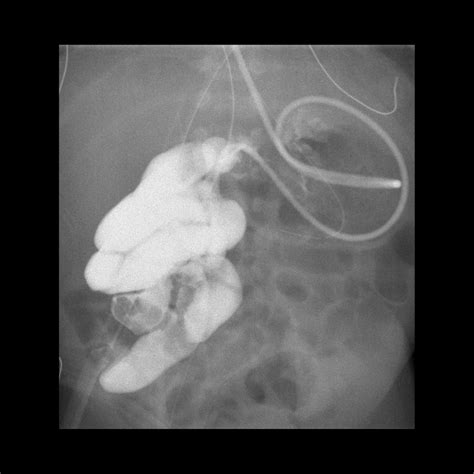

Diagnostic Imaging and the Ligament of Treitz

Radiologists rely on the Ligament of Treitz when interpreting imaging studies such as CT scans or fluoroscopy (barium swallow/meal). The position of the duodenojejunal flexure in relation to the vertebral column and the midline can provide diagnostic clues for anatomical anomalies. For instance, in a normal anatomical presentation, the flexure should be to the left of the midline and at the level of the L1 or L2 vertebrae.

When imaging confirms that the flexure is located to the right of the midline, it is a hallmark sign of intestinal malrotation. Recognizing these signs early through imaging can prevent life-threatening complications, especially in pediatric patients who are born with congenital intestinal positioning issues.

• ligament of treitz fluoroscopy

• ligament of treitz x ray

• ligament of treitz radiology